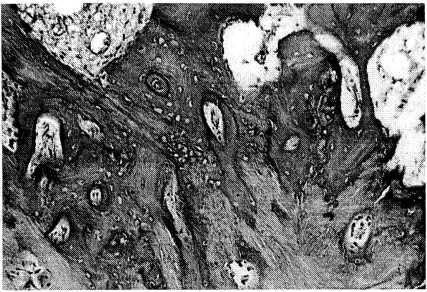

Рис. 1. Гетеротопическая кость, по строению близкая к кортикальной кости, отличающаяся незрелостью, неравномерным обызвествлением и расположением остеоцитов, отсутствием линий склеивания. Здесь и на рис. 2: окраска гематоксилином и эозином. Ув. 100.

При морфологическом исследовании гетеротопических оссификатов выявлена в основном незрелая новообразованная кость с неполноценной архитектоникой: пластинчатое строение отсутствует, каналы кости отличаются разнонаправленной ориентацией, остеоциты распределены неравномерно (рис. 1). Линии склеивания малочисленны, имеют неровный, ломаный характер, межклеточный матрикс кости окрашивается неравномерно (рис. 2), в межбалочных пространствах рыхлая клеточно-волокнистая ткань с избыточным содержанием сосудистых элементов. Поверхность кости неровная, часто обнаруживаются лакуны резорбции, содержащие остеокласты и гистиоциты. Вблизи новообразованной кости в элементах соединительнотканных волокон выявляются разрозненные, малодифференцированные клеточные элементы мезенхимального происхождения, которые, повидимому, постепенно превращаются в хрящевые и костные клетки, поскольку именно в этих участках наблюдается активное образование и обызвествление гетеротопической кости.